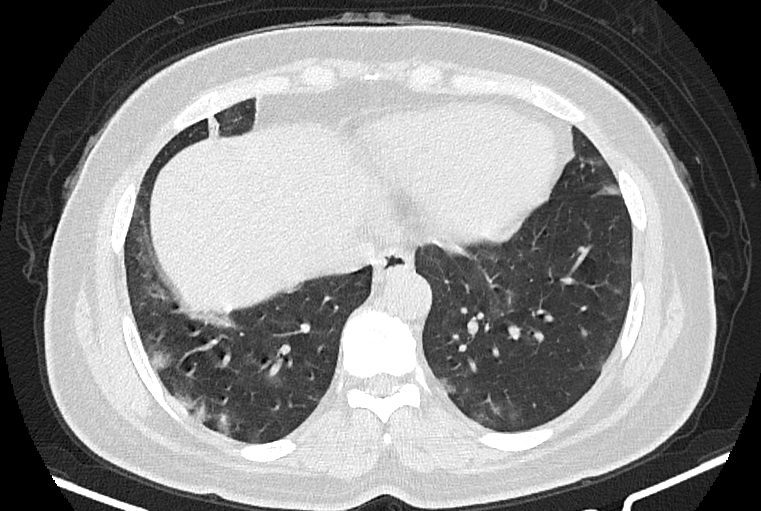

در HRCT از ريه ها(اسپيرال ، مولتي ديتکتور 16، مقاطع اگزيال با ضخامت 1mm بدون فاصله ) ، بدون كنتراست تزريقي :

-Ground glass opacities Patchy پراکنده در ريه ها مشهود است که مطرح کننده Viral pneumonia مي باشد . ( با درگيري 20 درصد حجم ريه )

-کلسیفیکاسیون دیواره آئورت و عروق کرونر ، تغییرات DJD در ستون فقرات ونشانه های CABG مشهود است .

نتیجه : Highly suggestive of COVID-19